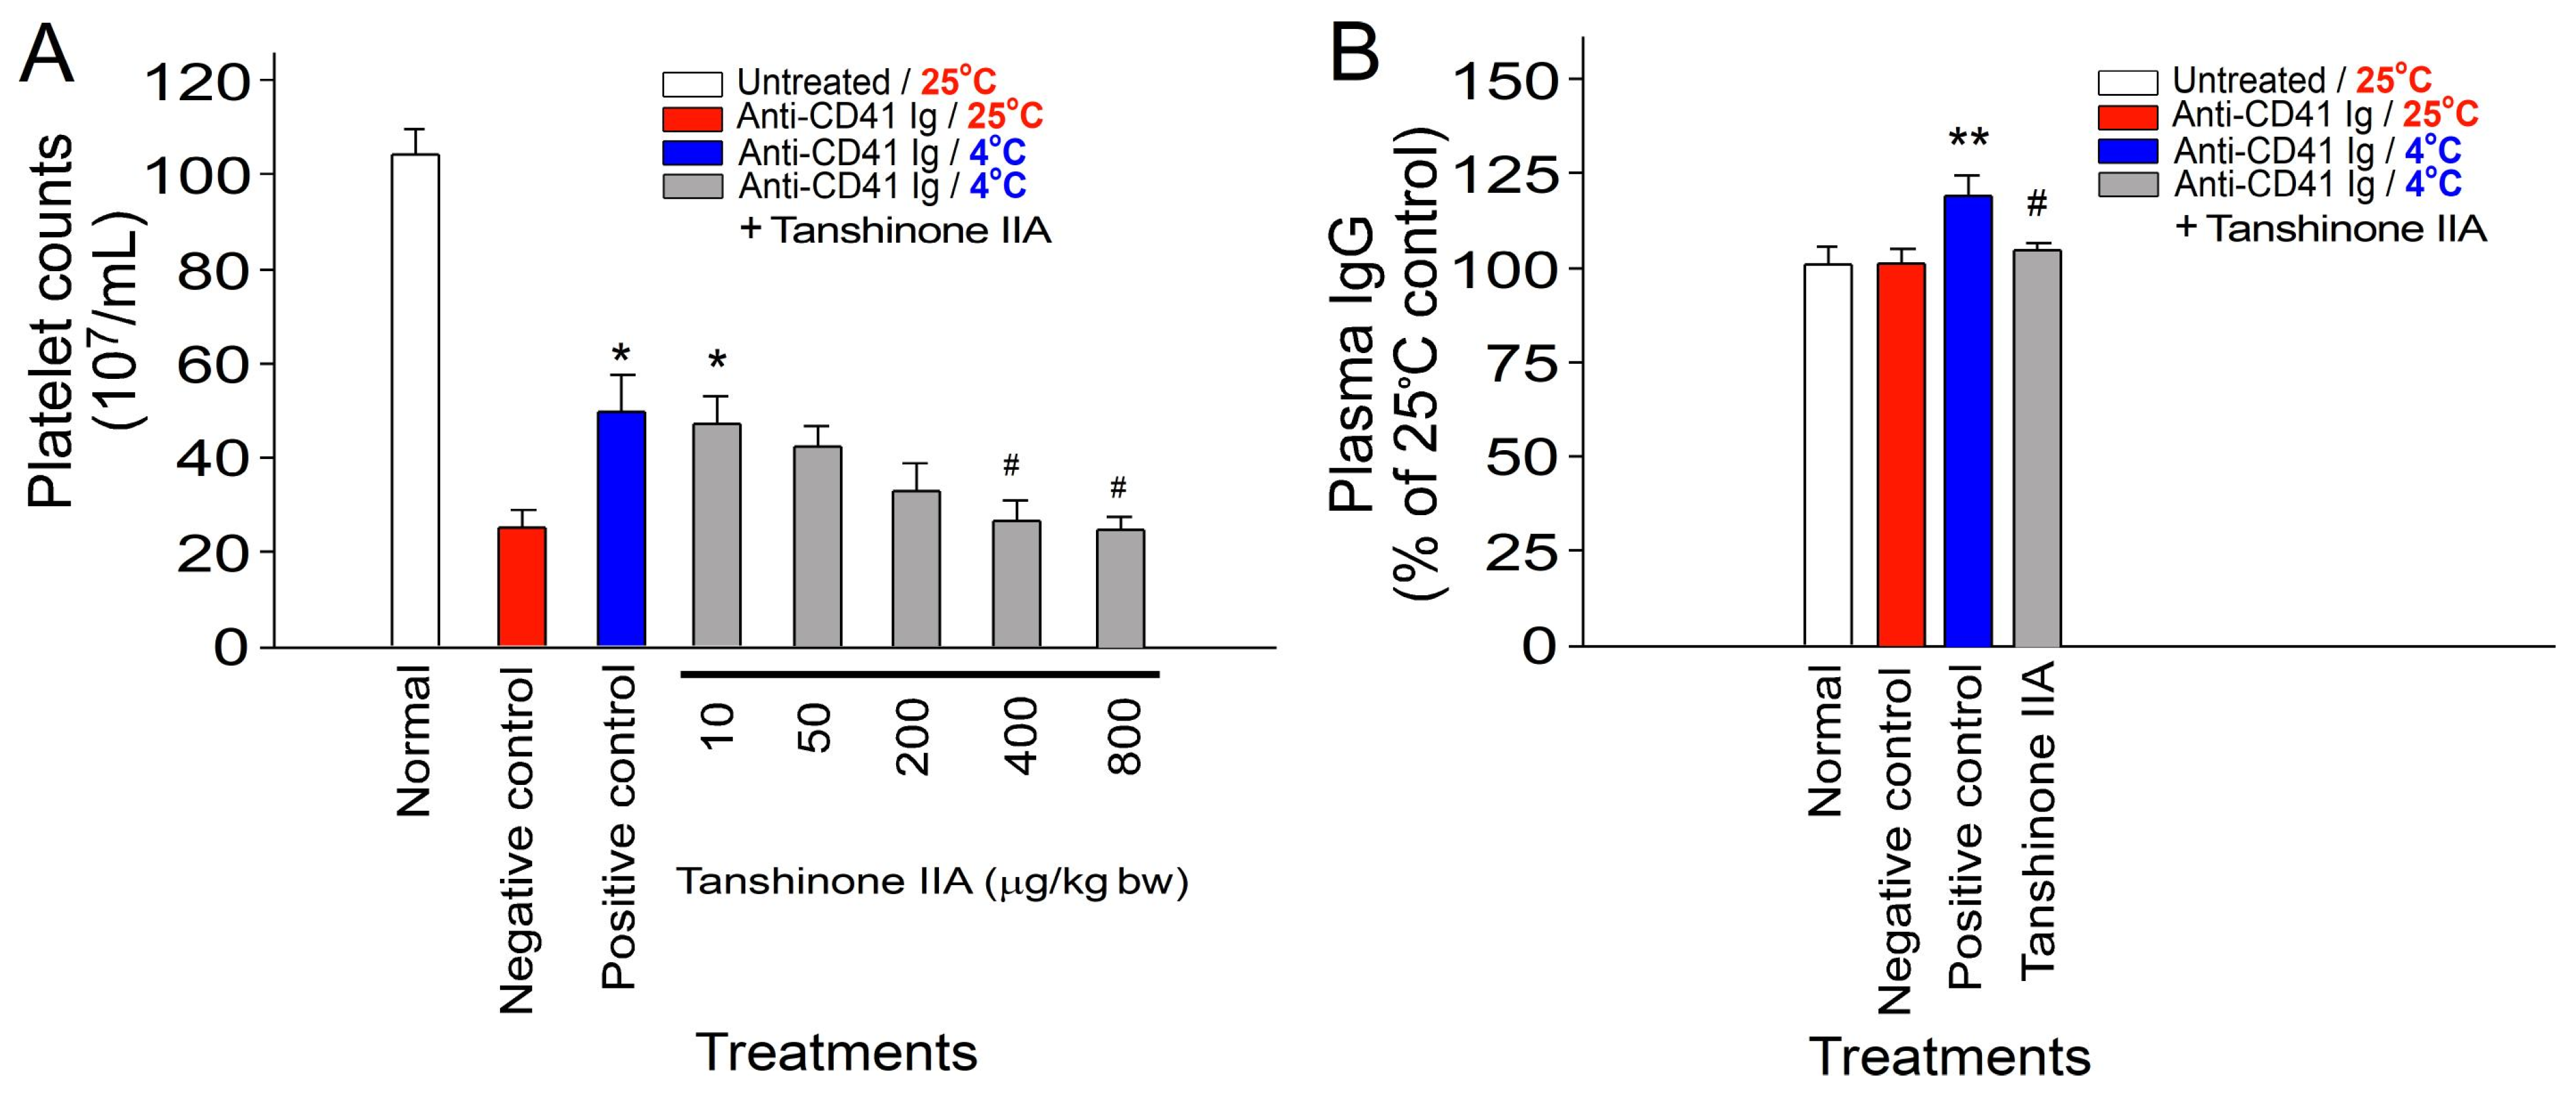

2.2. Reversal of Cold-Induced Immunosuppression in Mice through Treatment with a S. miltiorrhiza Root Component Tanshinone IIA

4.5. Tanshinone IIA, and S. miltiorrhiza Root Ethanolic Extract